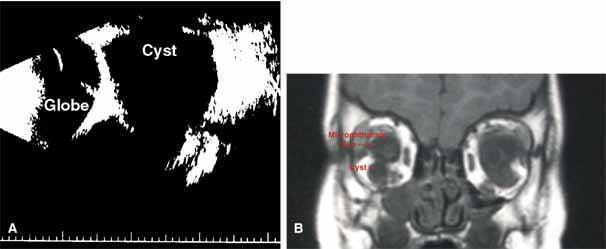

“Microphthalmia with cyst” refers to cases of colobomatous microphthalmia with a posterior eye wall defect through which a cyst lined with neuroectodermally derived tissue protrudes into the orbit. These cysts may be small and only detected by imaging (Fig. 2); sometimes, they may be large enough to cause progressive proptosis. Most cases are isolated, but familial occurrences have been reported.67–69 Inheritance is likely autosomal recessive. Depending on the size of the cyst, its appearance, and the visual potential of the microphthalmic eye, these cysts may be managed by observation, excision with or without enucleation, and/or aspiration.70 Aspirated cysts tend to reaccumulate fluid. Socket expansion improves cosmesis.

|